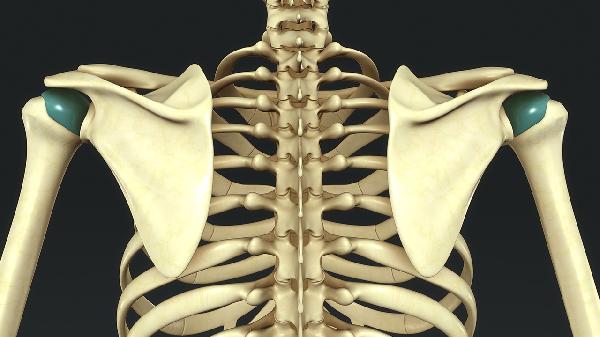

胸椎痛可能由肌肉劳损、骨质疏松、胸椎间盘突出、胸椎关节紊乱、强直性脊柱炎等原因引起。胸椎痛通常表现为局部疼痛、活动受限、放射痛等症状,可通过物理治疗、药物治疗、手术治疗等方式缓解。